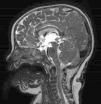

Se presenta el caso de un niño de 16 meses nacido en España, atendido en urgencias por somnolencia desde hace 8 h en el contexto de fiebre y tos de 5 días de evolución. El paciente había presentado 3 meses antes una adenitis cervical con mala respuesta a la antibioterapia, seguida de tos persistente en accesos, sin otros antecedentes de interés. En la exploración física destaca una disminución del nivel de consciencia (escala de coma de Glasgow, 12 puntos), alteración de la mirada conjugada y signos meníngeos positivos. La analítica de sangre presenta 11,4×103/μl leucocitos (39,1% linfocitos; 17,8% monocitos; 41,8% segmentados) y PCR 5,3mg/dl, con resto de bioquímica normal. La tomografía computarizada craneal muestra hidrocefalia tricameral no comunicante, con una imagen hiperdensa obstruyendo el acueducto de Silvio, compatible con gliosis reactiva secundaria a exudado inflamatorio (fig. 1). Ante el cuadro de hipertensión intracraneal con deterioro neurológico progresivo, se coloca de urgencia un drenaje ventricular externo. El LCR ventricular presenta una bioquímica normal (glucosa 83mg/dl, proteínas 20mg/dl), sin leucocitos ni gérmenes en la tinción de Gram. Pese a ello, dado el antecedente de adenoflemón de curso tórpido, la meningitis con hidrocefalia aguda y la linfomonocitosis se sospecha una meningitis tuberculosa y se inicia tratamiento empírico con vancomicina, cefotaxima y 4 tuberculostáticos (isoniazida, rifampicina, pirazinamida y etambutol), así como dexametasona. Tras la intervención se recoge muestra de secreciones respiratorias por tubo endotraqueal, con radiografía de tórax normal pero PCR positiva para micobacterias al 4.° día de ingreso. El diagnóstico de meningitis tuberculosa se confirma posteriormente mediante PCR de LCR a los 7 días, con Ziehl-Neelsen y cultivos para micobacterias negativos, tanto en secreciones respiratorias como en LCR. La resonancia magnética de control muestra una disminución del tamaño ventricular y la estenosis del extremo distal del acueducto de Silvio (fig. 2). Al tercer día se coloca una derivación ventrículo-peritoneal, completando 2 meses de tratamiento con 4 fármacos y 12 meses de isoniacida y rifampicina, con controles posteriores de RM con resolución de la hidrocefalia y válvula funcionante, persistiendo signos de flujo hiperdinámico a nivel del acueducto de Silvio. En la actualidad presenta un desarrollo psicomotor normal para la edad.